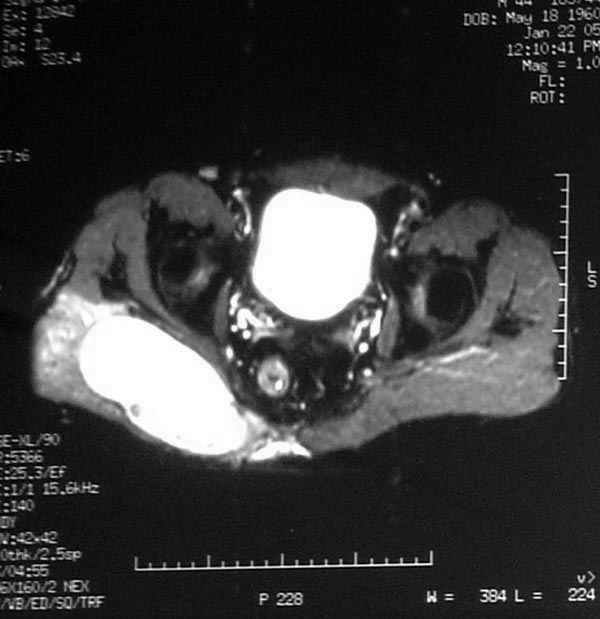

Уважаемые коллеги,Неоднократные пункционные эвакуация (3 раза) крови изягодичной области, после полученной пройзводственнойтравмы (более 1.5 мес) ударом в ягодицу тяжелым, около полутонны предметом.

Рентгенограмма без особенностей, несмещенные переломы лонной и седалищных костей таза.Последная пункция 10 дней назад 180 мл темной крови, после пункции сделано магнито-резонансные исследование (на снимках), какой диагноз и тактика дальнейшего лечения, какие рекомендации?Джолдас Кульджанов

Djoldas Kuldjanov, M.D. 06 Март 2005, 00:25

Разбираемый случай немного отличался от классического Degloving Injury

или Morel-Lavalle Lesion, которые часты при переломах ацетабулума и

костей таза. Состояние, наблюдаемое после удара, в результате чего

образуются обширные полости в тазобедренной области: ягодицы или

большого вертела. Как описал Анатолий, обширные полости заполняются

кровью, затем синовиальной жидкостью, отодвигают сроки операции или

после операции приводят к осложнениям послеоперационных ран.

Описанный случай:

В промежутке около месяца 3 пункции с удалением около 180 мл крови

каждый раз. После исследовании МРТ было принято решение - удаление

гематомы в операционной более широким доступом. Во время операции -

под ягодичной мышцей была капсула, где скопилось около 700 мл

гематомы, после удаления в полости обнаружили несколько закупорившихся

вен и краевой разрыв одной из двух ветвей нижней ягодичной артерии.

После промывания, гемостаза и дренажа, по рекомендации хирурга стенку

полости обработали спреем Tisseel, специальным склерозирующим

препаратом, применяемым пластическими хирургами, затем зашили рану.

Дренажи удалены на 5 день, рана зажила первично. Случай был интересен

применением препарата Tisseel Fibrin Sealant для склерозирования

полостей, только недавно получившим разрешение к применению, хотя по

аннотации в Европе и в Южной Америке применяют давно.